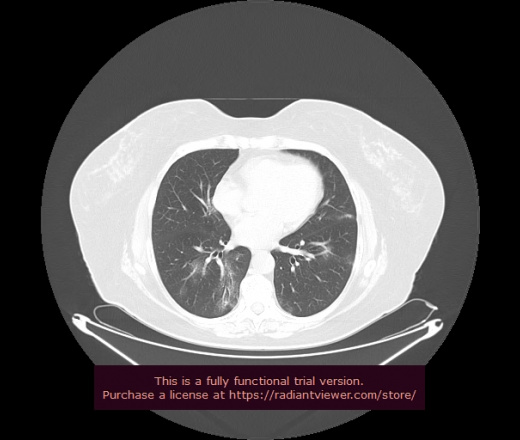

Уважаемые коллеги, если имеется интерес, сможете ли Вы спрогнозировать дальнейшее +-одинаковое течение процесса у 4 данных разных пациентов? Зацепиться где-то можно очень просто, где-то нельзя.